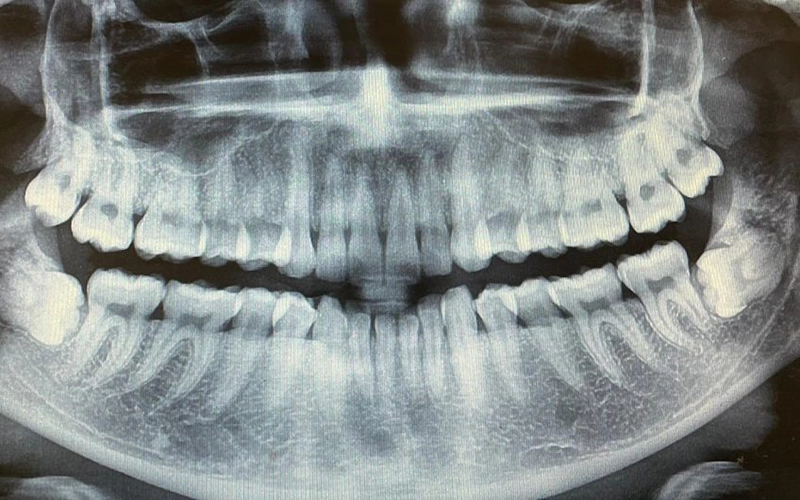

Not everyone requires wisdom tooth extraction. If your wisdom teeth are healthy, fully erupted, properly aligned, and easy to clean, they may not pose a risk. However, issues arise when these third molars grow at awkward angles, fail to erupt fully, or become impacted—leading to discomfort and potential oral health problems.

Wisdom teeth, located at the very back of the mouth, can place pressure on neighbouring teeth as they attempt to emerge. Partially erupted wisdom teeth often trap food and bacteria under the gumline, which can lead to infection or inflammation.

According to the Australian Academy of Dentistry, wisdom tooth removal may be necessary if you experience any of the following: